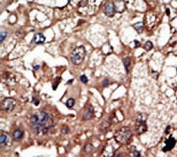

IHC testing of FFPE human cancer tissue with EPS8 antibody. HIER: steam section in pH6 citrate buffer for 20 min and allow to cool prior to staining.